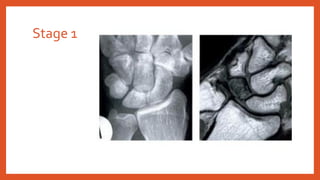

• Stage 1: Normal radiographs, diffuse changes in the signal intensity onT1 andT2

on MRI

Stage 1